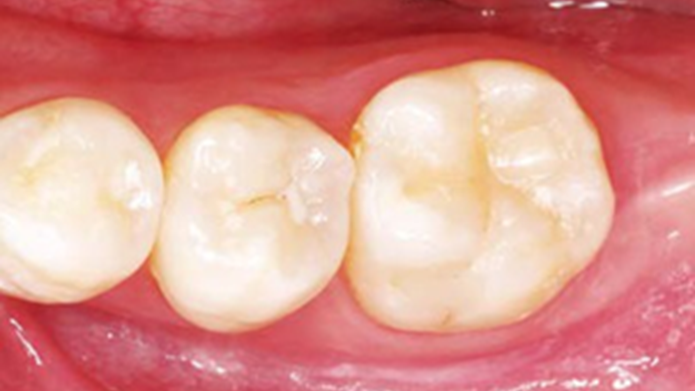

Clinical case: Bone growth in deepest thread of 8.0mm AnyRidge fixture

Clinical case: Bone filling into the bottom of deepest thread at 8.0mm AnyRidge fixture

- Courtesy of Dr. Kwang Bum Park -

Keywords

AnyRidge, Knifethread ,extraction socket, ,initial stability ,Allograft, ,osseointegratio ,Dr. Kwang Bum Park, , Mandibular, Single replacement, AnyRidge, Mega-oss,

Products used

Implant system-AnyRidge, Regeneration-Mega-Oss